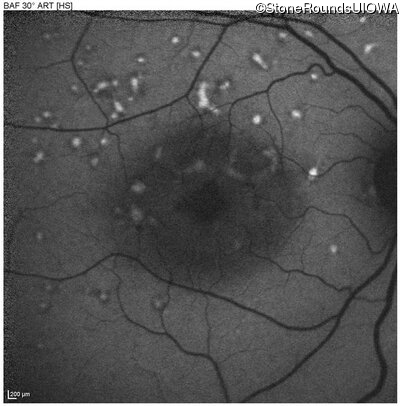

Age at visit: 49 years

This 49 year old man was first told he had a fundus abnormality on a routine eye exam at age 34. Ten years later he noticed some distortion just superior to fixation.

Age at visit: 49 years (Visit 2)

Pattern Dystrophy PRPH2 Gln239Stop CAG>TAG   AD